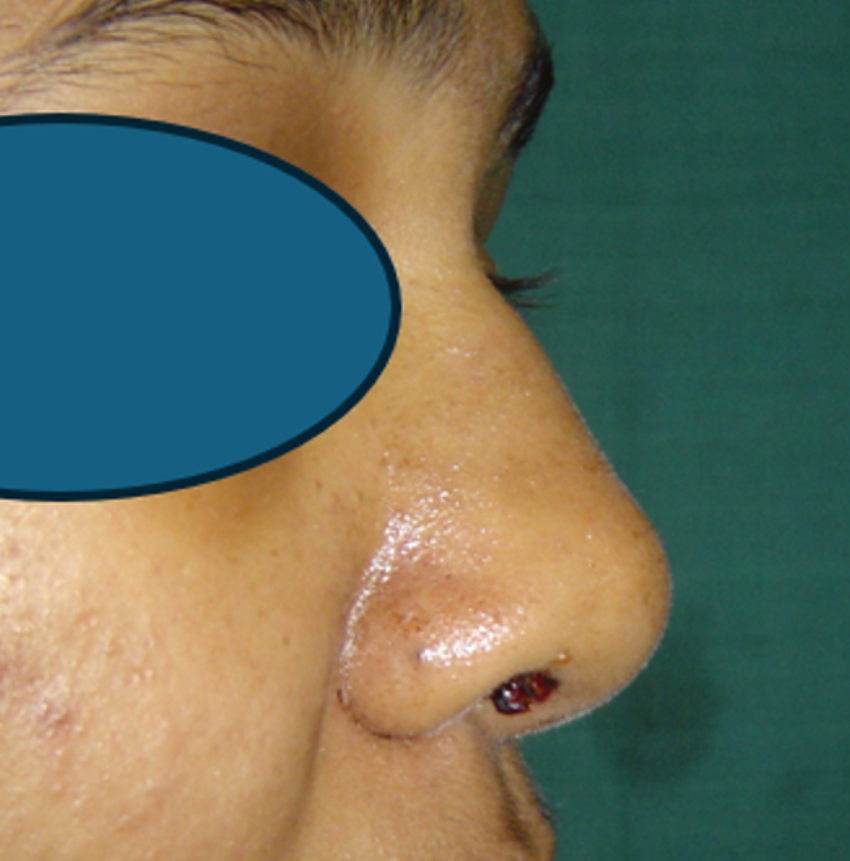

RHINOPLASTY

Cosmetic